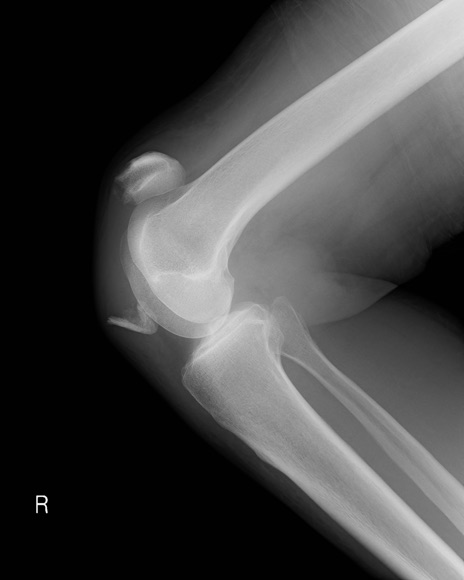

症例28 右膝関節レントゲン(側面像)

【症例】60歳代女性

【主訴】右膝痛

【現病歴】本日椅子より転落し受傷。右膝痛及び歩行困難となり来院。

【身体所見】右膝腫脹++、右足関節の運動は良好、感覚障害なし。

異常所見と診断は?

右膝関節レントゲン